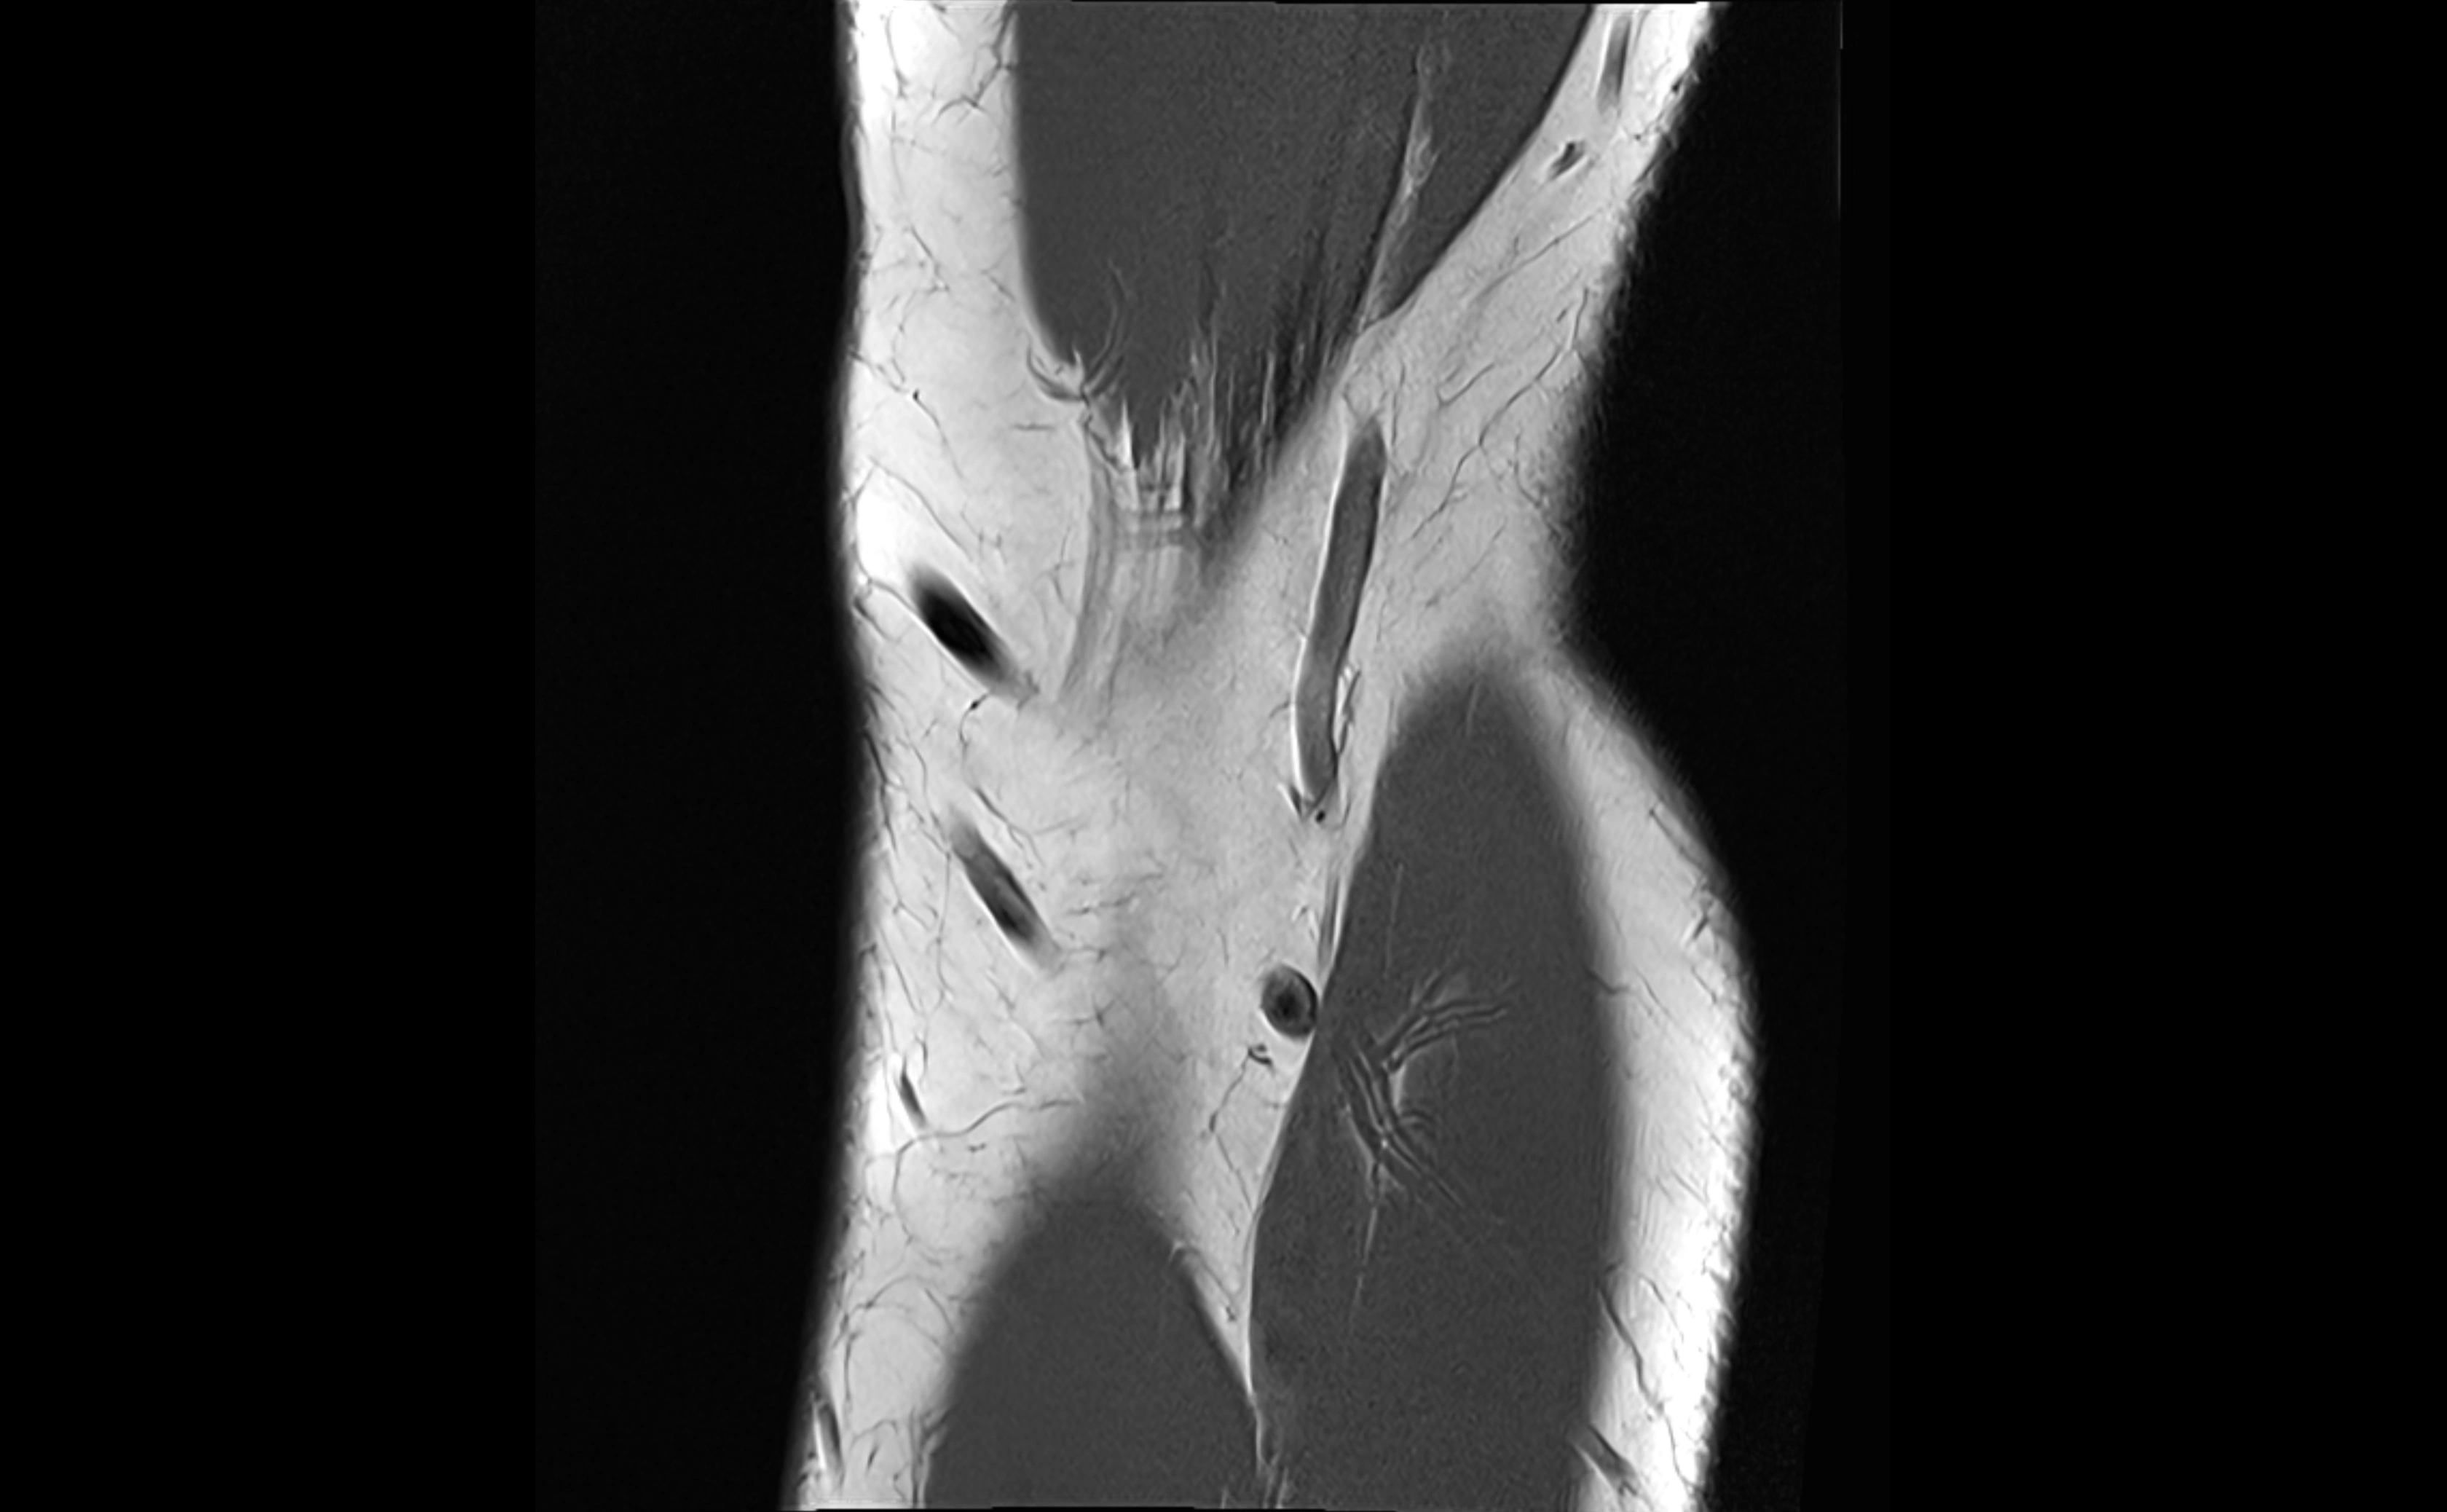

MRI images

image